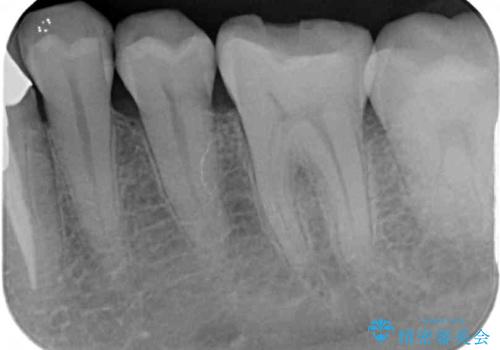

- 張り出している骨隆起による話しにくさを気にして来院された患者様です。

目視でも大きいと分かる骨隆起が認められたため、歯肉を切開した上で切除することとしました。

また、付近の歯に大きなむし歯が認められたため、セラミックインレーによる修復治療も行うこととしました。